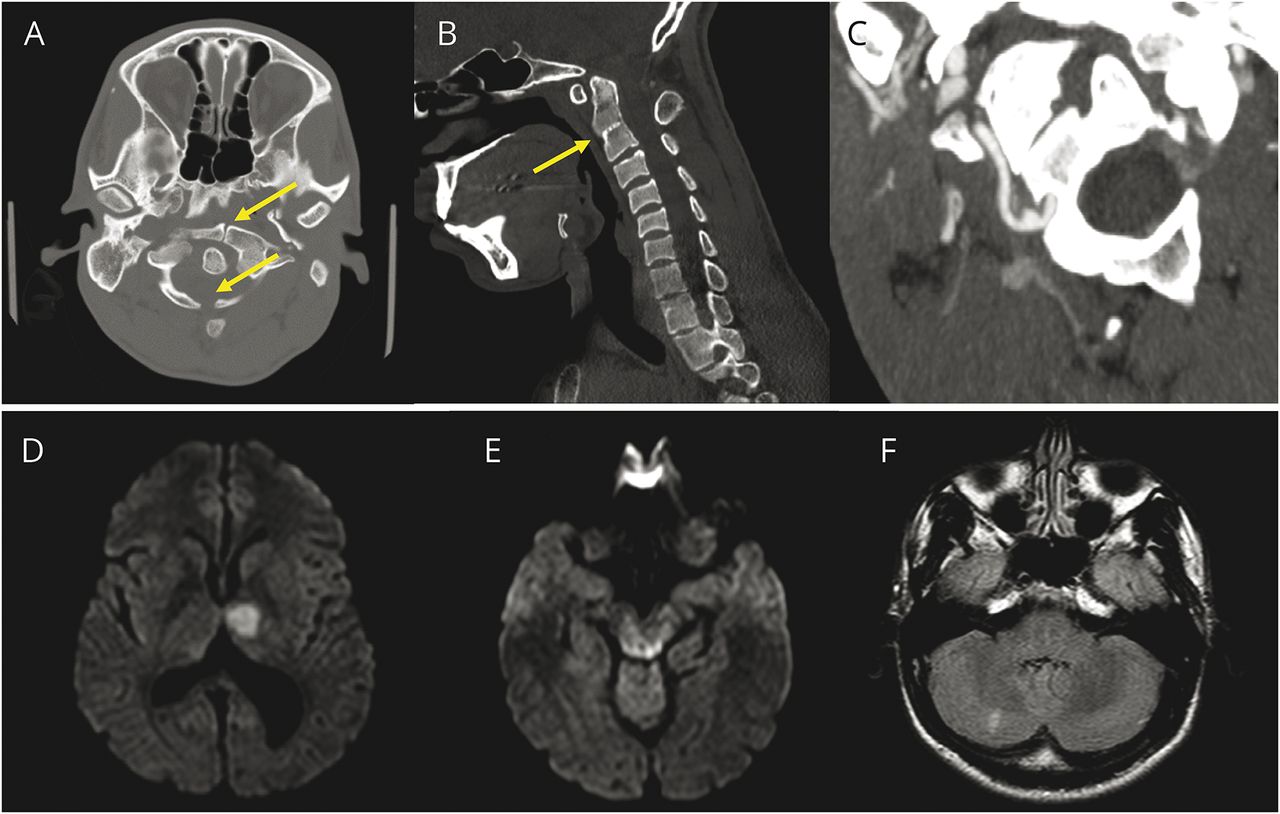

1例24岁男性,无相关病史,因头向左转后间歇性头晕一周就诊。在急诊室就诊当天,患者出现了严重的复视和定向障碍。一个月前,他曾报告过类似的投诉。患者无发热、皮疹、头痛或颈部外伤史。患者无类似疾病、血管或结缔组织疾病、中风样发作、癫痫或早发性痴呆家族史。检查显示轻度认知障碍和右侧偏瘫。初次头部CT显示先天性寰椎骨不连(C1)伴第二和第三椎体融合(C2-C3)。脑MRI显示左丘脑和双侧中脑背侧弥散受限,提示多发急性梗死。慢性梗死也出现在右小脑,这表明先前的缺血发作。一系列动态x线显示寰椎侧块与C2对齐不良,但没有不稳定的证据。 CT angiography (CTA) revealed the presence of a pseudoaneurysm of the right VA at its exit from the C2 transverse foramen. This was suspected to be the source of the posterior circulation emboli. Left VA was unremarkable. There was no evidence of VA dissection on CTA (数字).磁共振血管造影(MRA)与颈部脂肪抑制图像未进行。其余检查包括全血细胞计数、血清化学和血脂、糖化血红蛋白水平、肝功能检查、高凝研究、d -二聚体水平、经胸超声心动图和短期动态心电图监测均无显著性变化。由于担心进一步的颈部操作,没有进行经食管超声心动图检查。

(A) CT颈椎显示C1椎骨不连(箭头)。(B)颈椎CT显示C2-3椎体融合(箭头)。(C)颈部CT血管造影显示右侧椎动脉假性动脉瘤,它从C2横孔出来。(D)扩散加权MRI显示急性左丘脑梗死。(E)扩散加权MRI显示急性背侧中脑梗死。(F)液体衰减反转恢复MRI显示慢性右小脑梗死。

临床诊断为BHS。阿司匹林用于继发性中风预防,患者被转诊进行颈椎矫正手术评估。大约1周后,患者因新的小脑梗死返回外部医院。数字减影血管造影(DSA)证实了右VA假性动脉瘤,怀疑是由他在颈部旋转时先天性颈脊髓异常对右VA的重复性机械损伤引起的。动态闭塞的VAs不能再现在血管造影和脊柱手术推迟。他接受保守治疗,使用阿司匹林和颈部固定,随访3个月未复发。